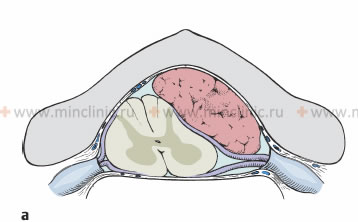

ხერხემლის არხის სიმსივნეები იყოფიან პირველად და მეორეულ (მეტასტაზები) სიმსივნეებად. ეს სიმსივნეები შეიძლება ლოკალიზებული იყოს ზურგის ტვინის მყარი გარსის ზევით (ექსტრადურალური ან ეპიდურალური) ან ქვევით (ინტრადურალური). გარსქვეშა (ინტრადურალური) სიმსივნეები შეიძლება განლაგებული იყოს ზურგის ტვინის პარენქიმის გარეთ ან შიგნით (ექსტრამედულარული, ინტრამედულარული).

ინტრადურალური ექსტრამედულარული სიმსივნით ზურგის ტვინის დაზიანების დასაწყისში ავადმყოფებს უვლინდებათ მგრძნობელობის ფესვური დარღვევა და ასიმეტრიული ნევროლოგიური დარღვევების სინდრომი. ზურგის ტვინის კომპიუტერული ტომოგრაფიისა და მიელოგრაფიის დროს ვლინდება ზურგის ტვინის სუბარაქნოიდულ სივრცეში მდებარე სიმსივნის საწინააღმდეგო მხარეს ზურგის ტვინის გადაადგილების (დისლოკაციის) ტიპური სურათი.